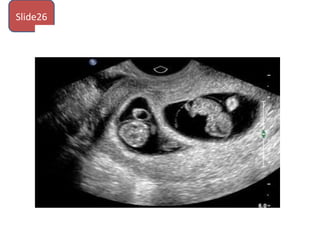

Slide26

1. What do you see in this photo ?

2. What type of zyogsitiy?

3. What is the choroncity? How to determine

it antenatal? And postnatal

1. What doyou see in this photo ? 2. What type of zyogsitiy? 3. What is the choroncity? How to determine it antenatal? And postnatal Slide26